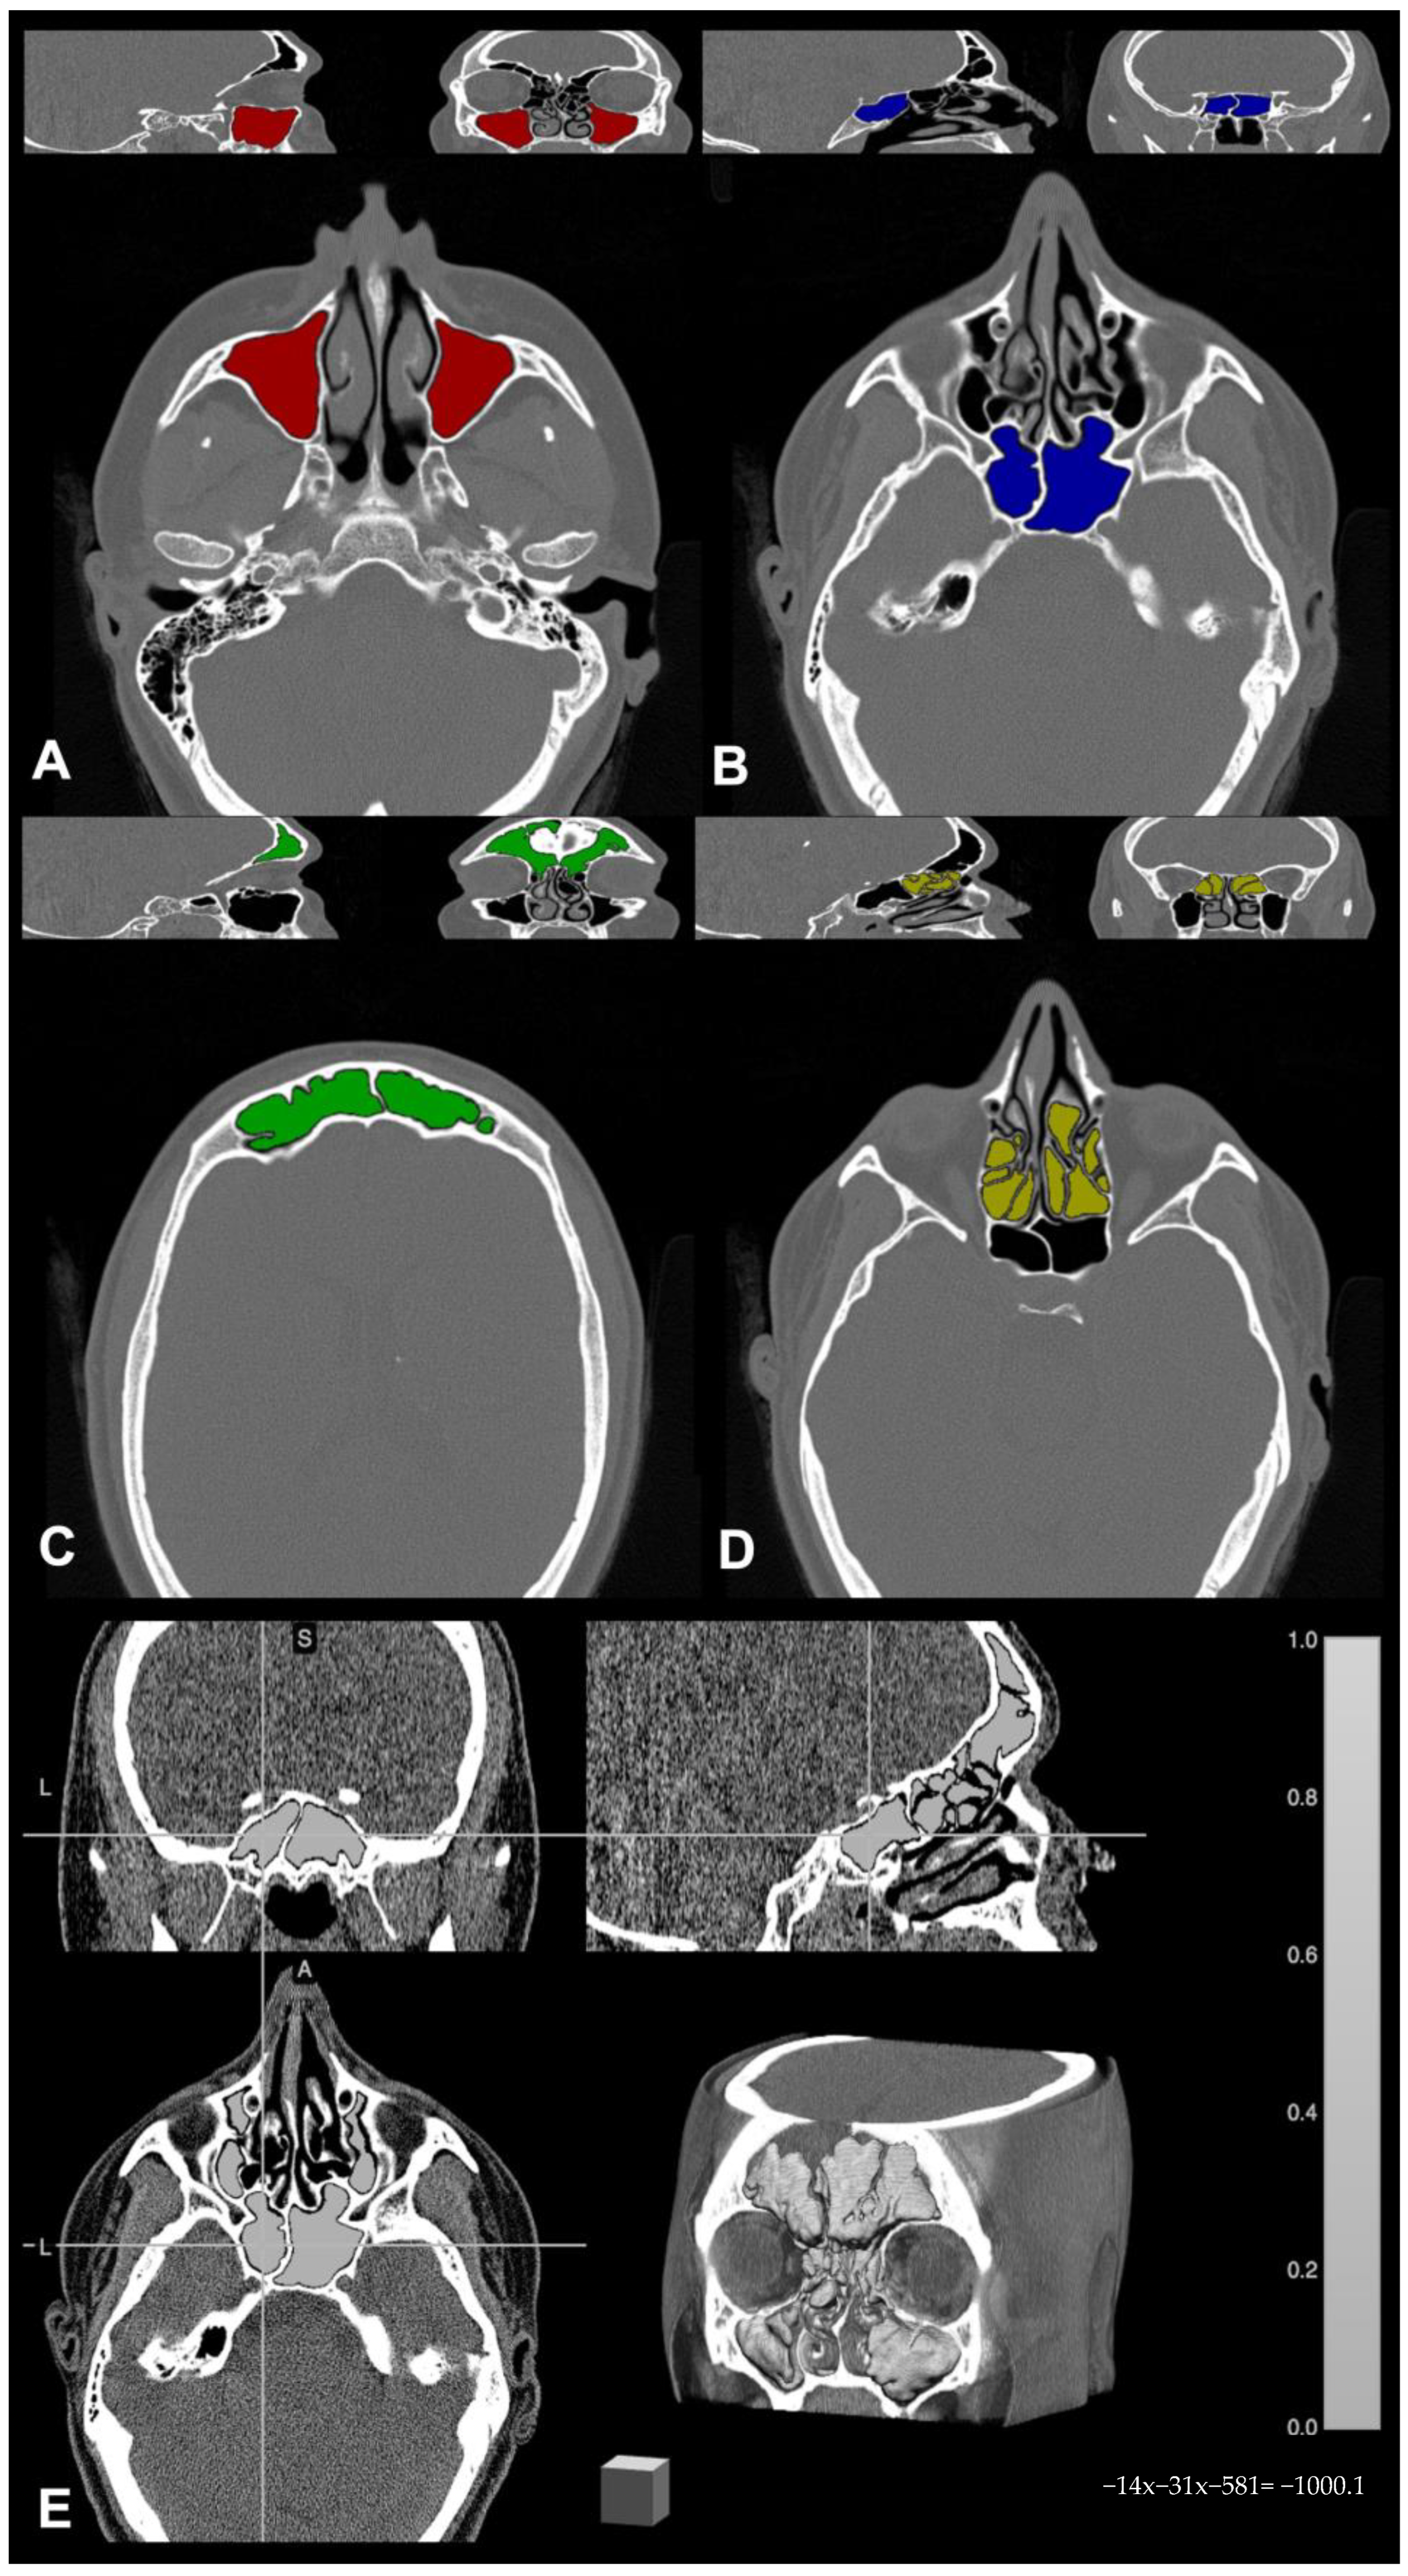

2.2. CT-Based Volumetric Assessment

Paranasal sinus CT scans were stored and anonymized, then converted from DICOM to NIfTI format by using the free online tool dcm2niix (https://www.nitrc.org/plugins/mwiki/index.php/dcm2nii:MainPage, (accessed on 15 March 2020)). For each CT examination, paranasal sinuses were individually segmented by an experienced neuroradiologist, and masks were drawn on each scan using the freely available software MRIcron 2019 (https://www.nitrc.org/projects/mricron (accessed on 15 March 2020)). In detail, bony landmarks were identified to delineate the sinus on the axial CT scan slice that contained one or more cavities, and the area inside such boundaries was filled automatically using the specific tool in the same software; these manually segmented sinus cavities constituted the region of interest (ROI) binary masks for each sinus. In case of mucosal thickening or sinus occlusion, binary masks of occupancy in the ROIs were also generated with the same procedure, and ROI masks were subsequently combined with the occupancy masks to remove any boundary inconsistencies [26]. Once completed, sinus masks were independently saved in the volume of interest (VOI) file format, and these VOI masks were used for calculating the computational volumes; namely, the output concerning each sinus was saved in a report of volumetric descriptive data for further statistical analysis. An example of segmentation showing the four sinus volume masks superimposed to the relative native CT examination is shown in Figure 1.

Figure 1. Example of paranasal sinus segmentation by means of MRIcron 2019 software (available at nitrc.org): (A) maxillary sinus (red); (B) sphenoid sinus (blue); (C) frontal sinus (green); (D) ethmoid sinus (yellow); (E) overall paranasal sinuses segmentation with three orthogonal plans and 3D reconstruction (light gray).